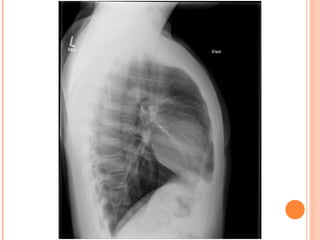

• #10 Hyperinflation is often best seen on the lateral chest radiograph with flattening of the diaphragms and expansion of the retrocardiac air space.